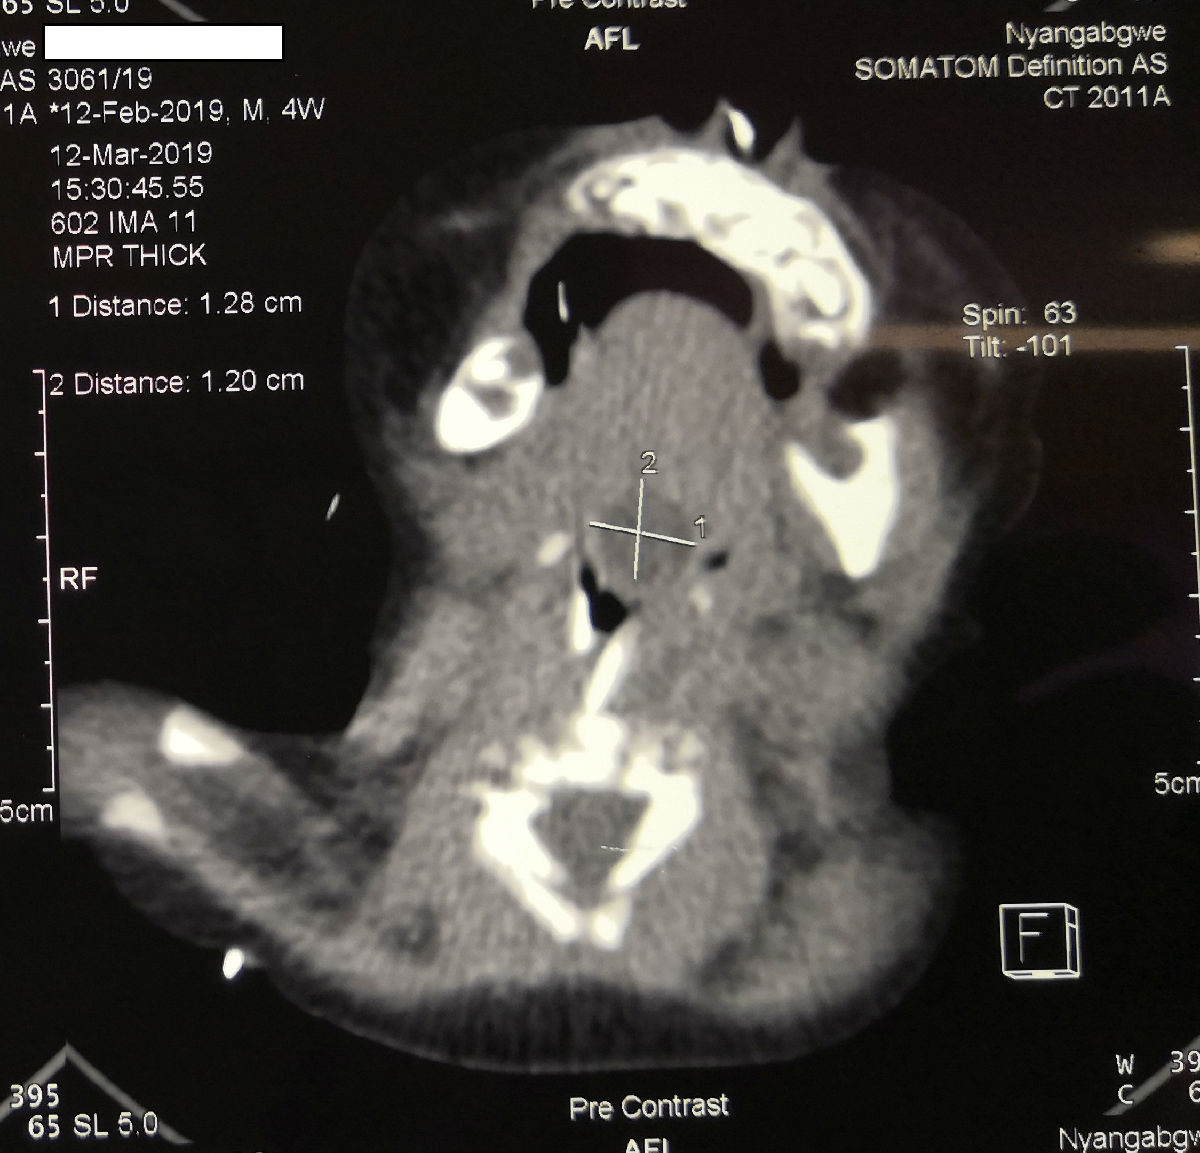

陳希杭是我院選派的第15批援博茨瓦納醫(yī)療隊(duì)哈博羅內(nèi)分隊(duì)隊(duì)員之一。前不久他為一位特殊患者進(jìn)行了手術(shù)。這是一名不到3個(gè)月大的嬰兒,因?yàn)樵谏喔块L(zhǎng)了一個(gè)巨大的囊腫,呼吸困難,如果不及時(shí)處理,可能隨時(shí)都有生命危險(xiǎn),患者的父母為此找了多家醫(yī)院,但是當(dāng)?shù)蒯t(yī)生都拒絕為其手術(shù)。陳希杭對(duì)患者進(jìn)行檢查之后,發(fā)現(xiàn)腫物位置很深,而且十分巨大,占據(jù)了患者的整個(gè)喉嚨,再加上當(dāng)?shù)蒯t(yī)院缺乏等離子刀等手術(shù)器械,因此手術(shù)難度很大。

陳希杭憑借多年的經(jīng)驗(yàn),想到可以利用吸引器套上塑料吸引器管,制作成一個(gè)電凝手術(shù)器械,并且利用小兒支撐喉鏡,盡可能微創(chuàng)地將舌根的巨大腫物切除。最終,經(jīng)過(guò)一個(gè)多小時(shí)的努力,手術(shù)成功完成。三天后,患者順利拔除氣管套管,并且發(fā)出了清亮的哭聲?;颊叩募议L(zhǎng)聽(tīng)到哭聲之后,非常高興。當(dāng)?shù)蒯t(yī)生也紛紛稱(chēng)贊中國(guó)醫(yī)療隊(duì),稱(chēng)這是“一次不可思議的手術(shù)!”